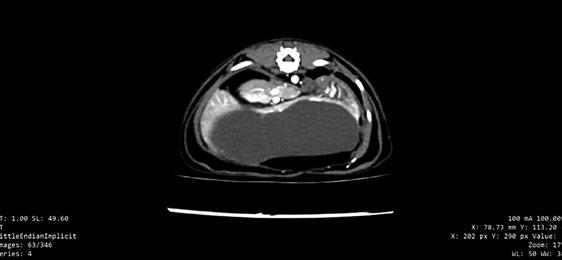

T-POCUS

Se optó por una T-POCUS al no considerar al animal lo suficientemente estable para realizar radiografías y ecocardiografía completa. En decúbito esternal para evitar el estrés. Se observaron gran cantidad de líneas B compatibles con presencia de

líquido intersticial pulmonar (más de tres por campo pulmonar), lo cual es compatible con edema pulmonar cardiogénico o no cardiogénico, procesos inflamatorios o infiltrativos (traumatismos, SRIS, bronquiolitis) o fibrosis intersticial. Se confirmó hipertrofia del VI y dilatación de AI. El aumento del AI junto con la presencia de líneas B puede sugerir con mayor probabilidad un edema pulmonar de origen cardiogénico (Ward et al. 2017).

La T-POCUS cada vez tiene mayor uso en casos de ICC para su diagnóstico, mediante la visualización de líneas B en los diferentes campos pulmonares (Ward et al 2017), tal y como ocurrió en nuestro caso.

La prueba de elección para diagnosticar ICC es la radiografía torácica. En nuestro caso retrasamos su realización y realizamos una T-POCUS dada la inestabilidad del paciente. La T-POCUS cada vez tiene mayor uso en casos de ICC para su diagnóstico, mediante la visualización de líneas B en los diferentes campos pulmonares (Ward et al. 2017), tal y como ocurrió en nuestro caso.

La T-POCUS y el NT-proBNP son útiles para el diagnóstico de ICC en gatos con distrés respiratorio (Ward et al. 2018). En nuestro caso, un valor positivo al snap indica un valor de NT-proBNP superior a 240 pmol/L que enmarca al animal (muy probablemente) en una patología cardiaca. Actualmente se estudia un nuevo biomarcador de CMH, la Galectina-3 (Stack et al. 2023).